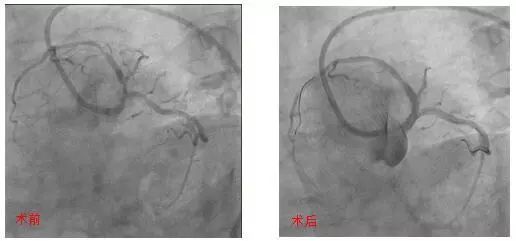

血管内超声引导下处理高危分叉病变

近日,72岁的那大妈因突发胸痛被送至北京大学国际医院急诊科,经急诊绿色通道,由心血管内科曲华清主任医师、杨泉主治医师迅速为她进行了冠脉造影,结果发现左主干、前降支、回旋支分叉处严重狭窄,回旋支血栓病变。因为病变复杂,且血流已恢复,医生建议择期进行手术。

冠脉左主干前三叉病变是介入治疗的深水区,术中稍有不慎可导致主干或分支闭塞,引发灾难性后果。目前国内国际介入专家对于此类病变的处理尚有争议,没有统一方案,手术的成功与否取决于术者的经验和操作技术。

曲华清主任医师凭借丰富的冠脉介入手术经验,术中应用血管内超声检查(IVUS)明确病变位置及各分叉斑块负荷,在IVUS的指导下,采用Crush技术在左主干-前降支和回旋支各植入1枚支架,使血流恢复通畅。手术圆满成功,那大妈恢复了以往的笑容。